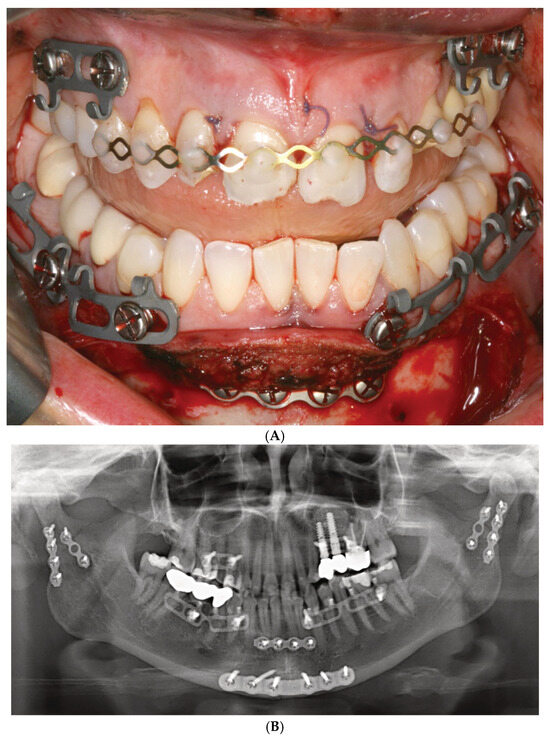

Figure 2.

(A) Clinical case example—Stryker SMARTLock Hybrid MMF System (regular size) in situ in a right condylar base fracture of the mandible. The arch bars are not shortened; several support legs (‘lugs’) have been bent along the length of their vertical axis to superimpose the screw-receiving holes over the interradicular spaces; all holes except from the right lower 2nd molar are filled with bone screws; the screws are lined up below the mucogingival junction in the upper jaw; in the mandible, the vestibules become shallow along the posterior bucco-alveolar sulcus, so these screws are placed in the mobile mucosa; in the anterior vestibulum, the screws are located low to reach down into the opening interradicular spaces; with such deep placement, the tooth equators cannot be attained. Preinjury occlusion with a lateral crossbite on the left is reestablished and maintained with anterior criss-cross elastic loop intermaxillary fixation. Note the kinking at the base of several bent supporting legs (‘lugs’). (B) Immediate postoperative panoramic X-ray after placement of SMARTLock arch bars. Miniplate fixation of right condylar base fracture (ORIF). Interradicular position of all arch bar retaining screws. In the upper right quadrant, 2 screws projecting over maxillary sinus. Eyelet of supporting leg (‘lug’) over right lower 2nd molar empty. Source/origin: Photograph collection—C.P. Cornelius.